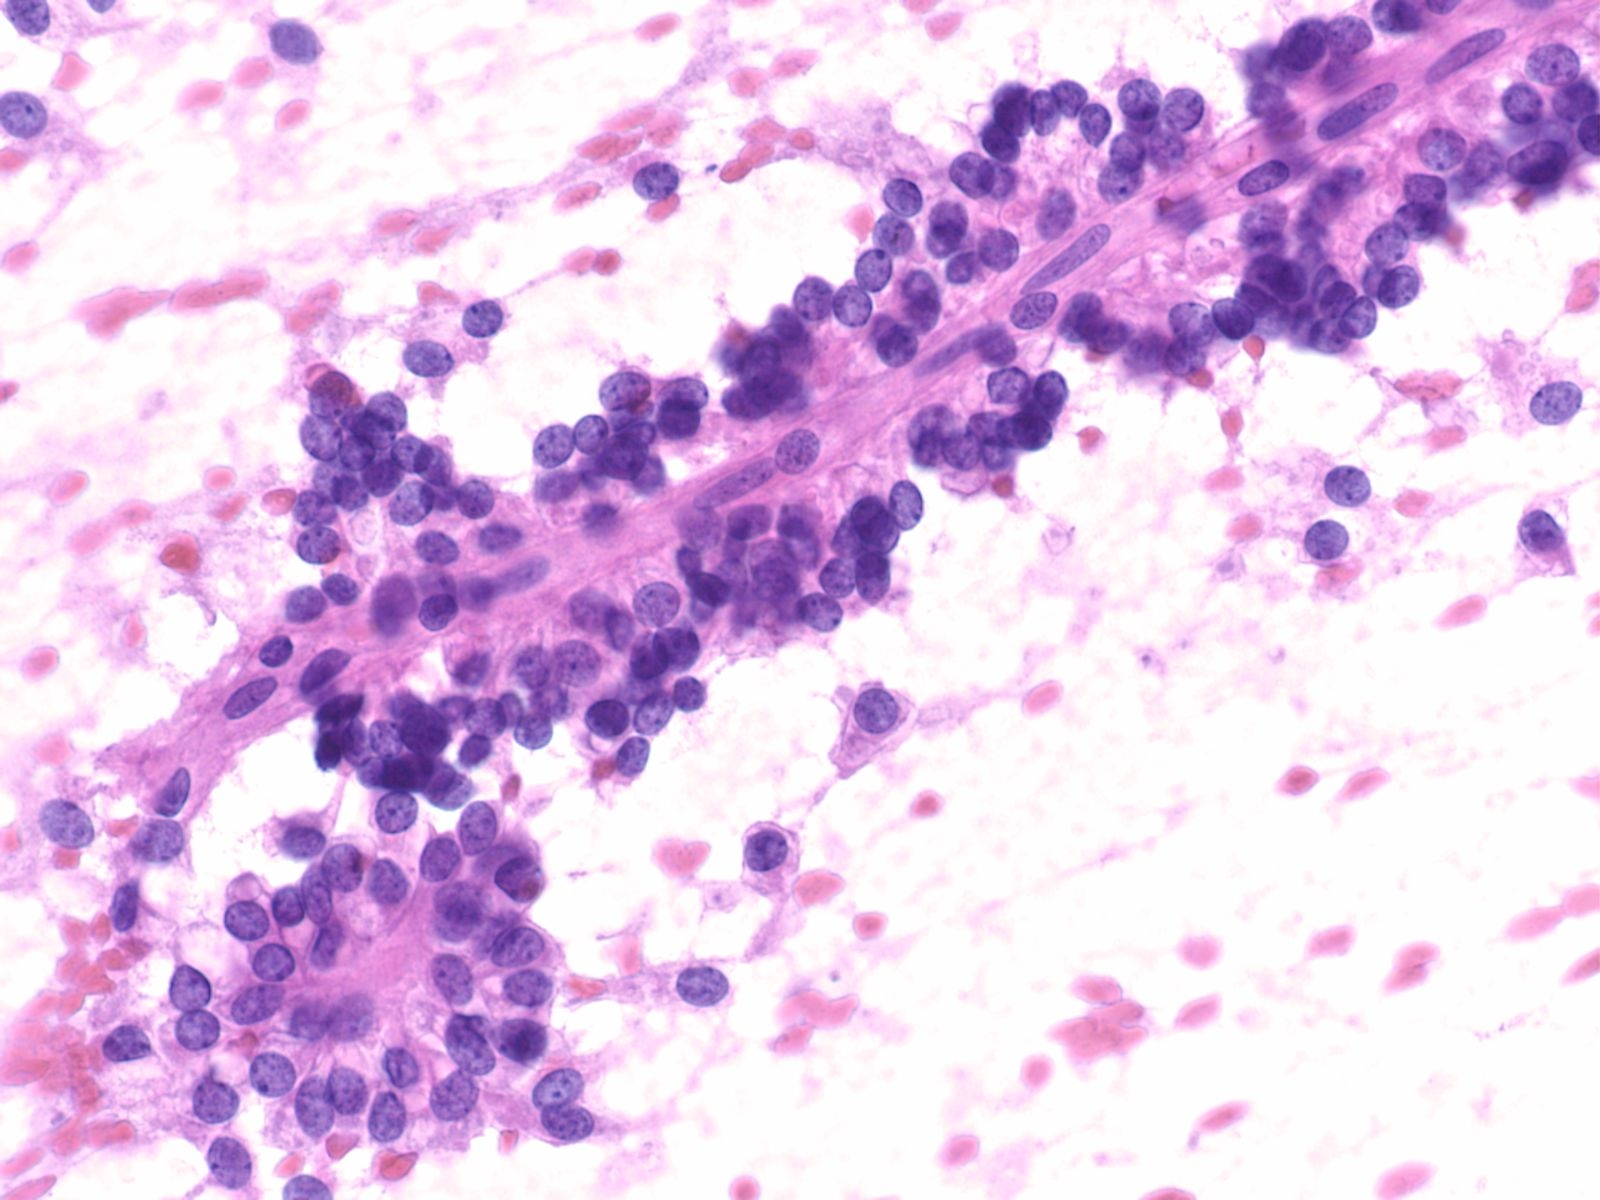

Neuroendocrine Tumor –MN07-R09706 and N13-6431

Key Cytological Features: Pancreatic Neuroendocrine Tumor

- Discohesive, single cell "solid-cellular "smear pattern

- Uniform, monotonous population of cells with plasmacytoid features

- Coarse, speckled, “salt and pepper” chromatin pattern

- Nucleoli may be prominent

- Dense, finely granular cytoplasm